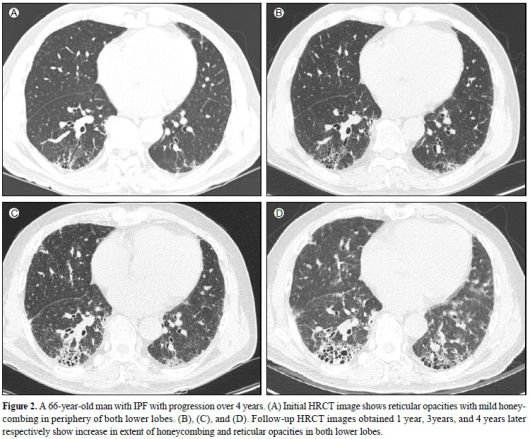

66세 특발성 폐섬유증 환자의 흉부방사선사진. 왼쪽 위(1년)부터 오른쪽 아래(4년)까지 병의 진행 상황을 볼 수 있다. 양측 폐에서 섬유화된 면적이 넓어지면서 병이 깊어진다. /고려대 안암병원 영상의학과 제공 |